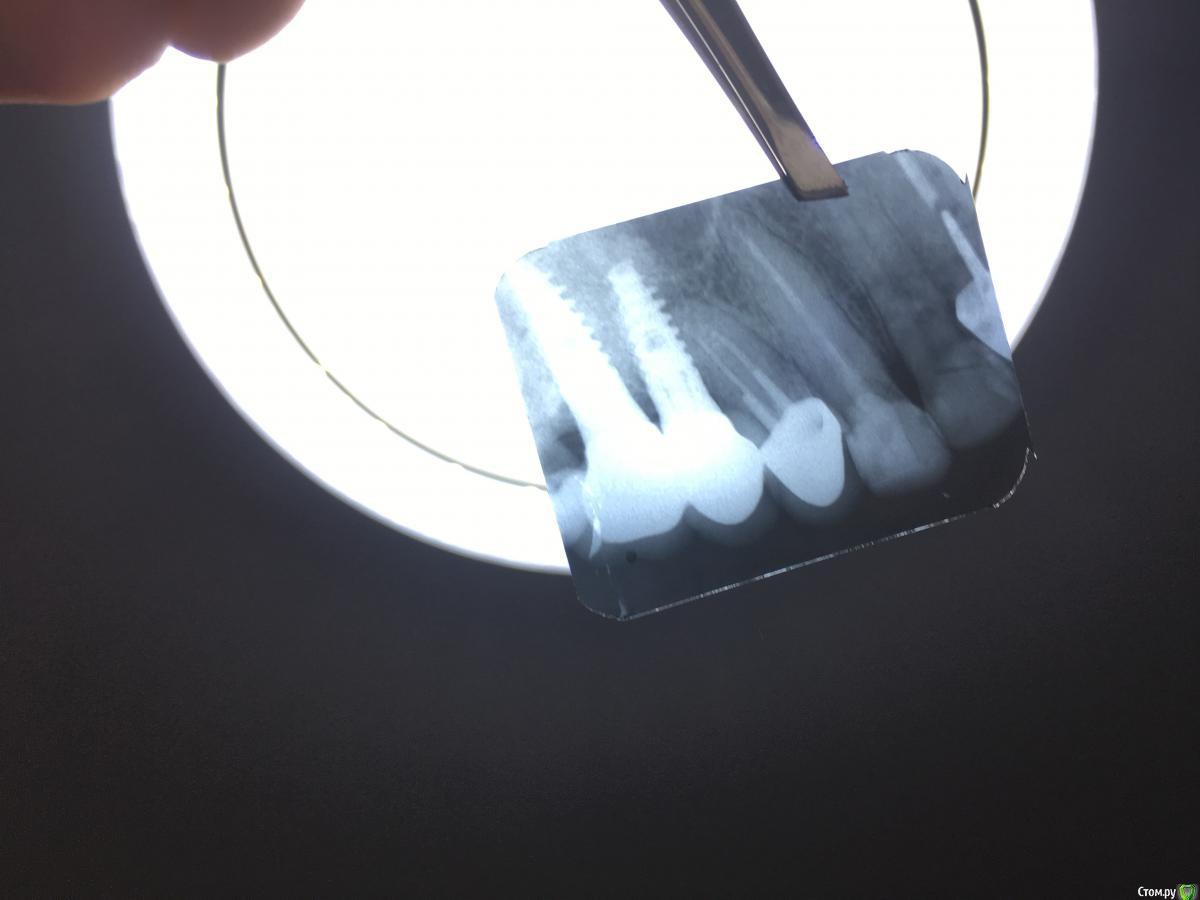

Kreveta Опубликовано 25 января, 2019 Автор Поделиться Опубликовано 25 января, 2019 Сделала ещё один снимок - перелом корня зуба, так что всё очень плохо((( Ссылка на комментарий

Kreveta Опубликовано 27 января, 2019 Автор Поделиться Опубликовано 27 января, 2019 (изменено) покажите? Изменено 27 января, 2019 пользователем Kreveta Ссылка на комментарий

Kreveta Опубликовано 27 января, 2019 Автор Поделиться Опубликовано 27 января, 2019 (изменено) Уже поставила имплант + временную коронку Изменено 27 января, 2019 пользователем Kreveta Ссылка на комментарий